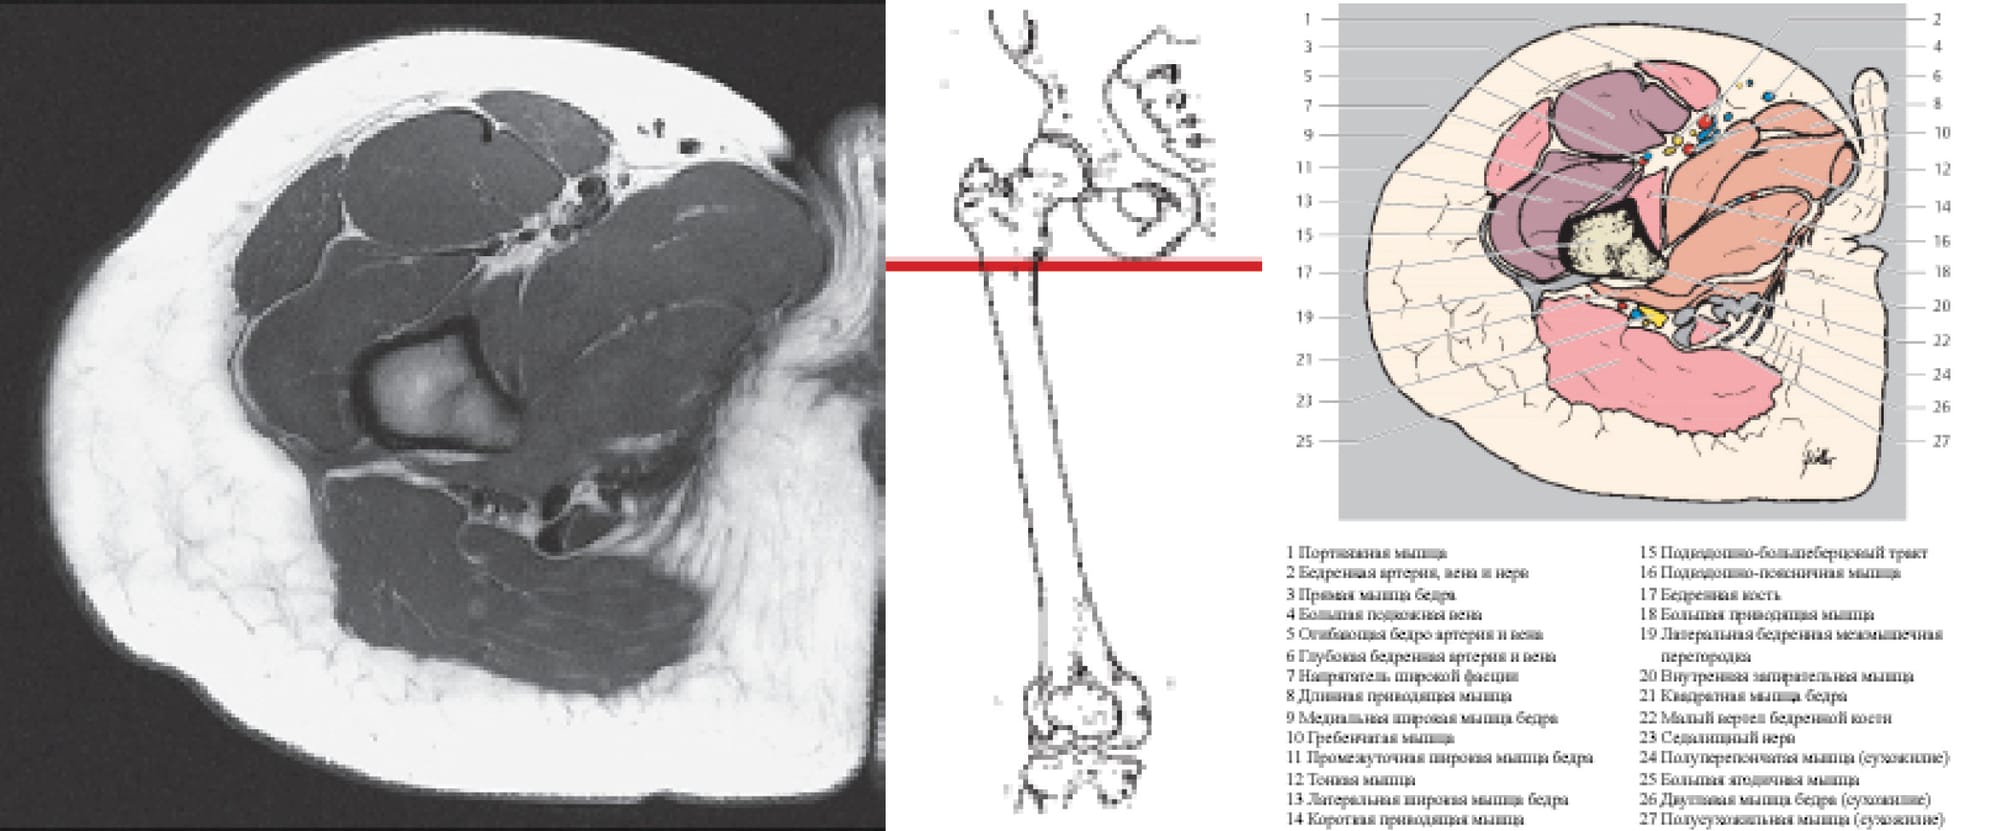

In the sectional anatomy atlas by Torsten B. Moeller (2000), a cross-section at the level of the lesser trochanter is shown (Figure 6).

The approach we used is indicated by arrows and passes, bypassing the main muscle groups of the thigh and neurovascular bundles. Particular caution is required when separating the m. quadratus femoris from the femur, as the sciatic nerve runs immediately behind it.